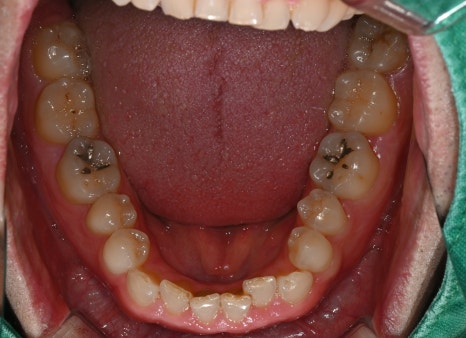

세 번째 사진: 초진 시 촬영한 하악(아랫니) 어금니 사진입니다. 아래 어금니 두 곳에서 충치가 진행되어 인레이 치료가 필요한 상태입니다.